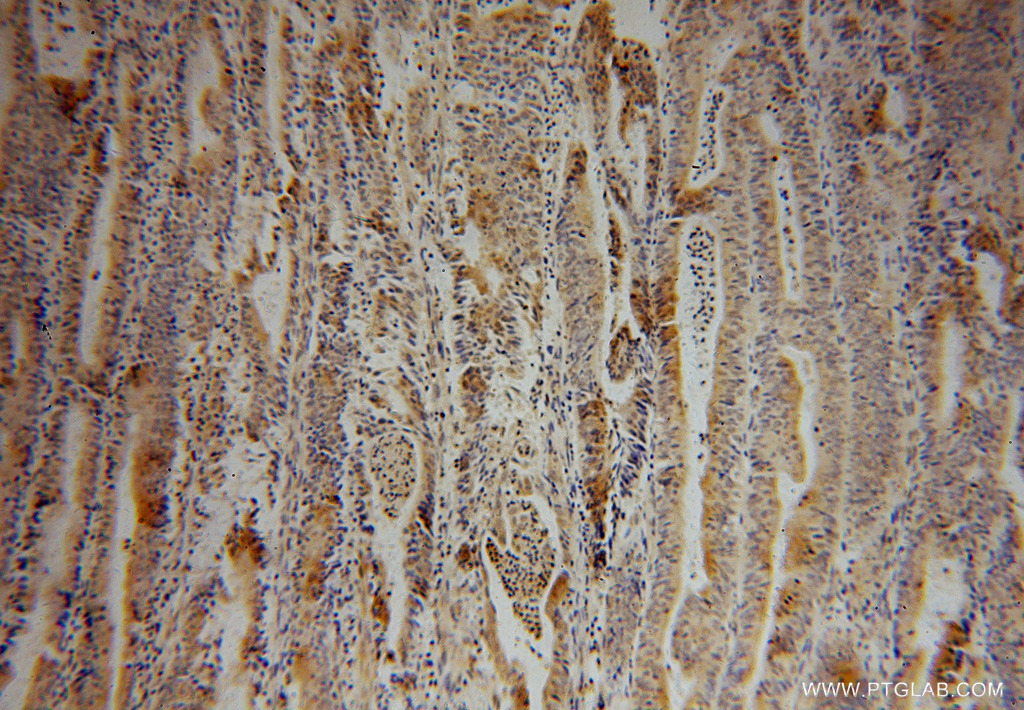

Supportive validation

- Submitted by

- Proteintech Group (provider)

- Main image

- Experimental details

- Immunohistochemical of paraffin-embedded human endometrial cancer using 15818-1-AP(UBA7 antibody) at dilution of 1:50 (under 10x lens)

- Sample type

- tissue